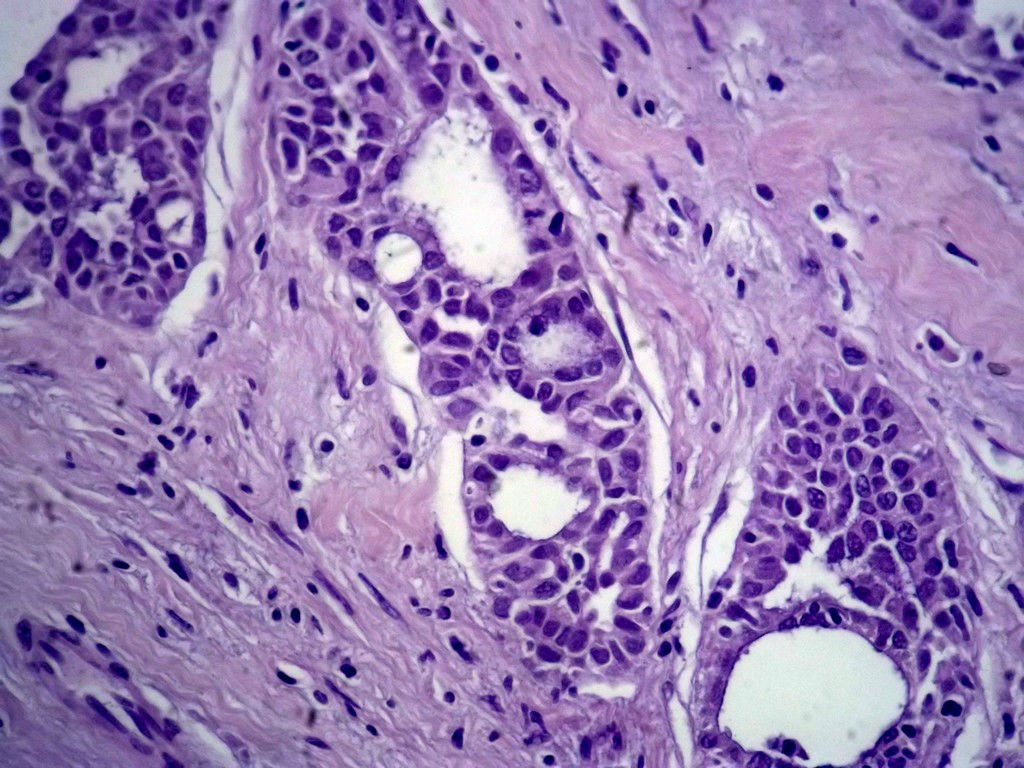

今天的一例术中冰冻。女,49岁,乳腺肿块。人气不旺,换个标题

腺病?癌?其他?(12楼常规,24楼免疫组化及会诊结果)图1

标签:浸润性导管癌 分泌癌 硬化性腺病

乳腺分泌型癌

导管是乎可见双层上皮,部分上皮增生并有一定异型,考虑硬化性腺病,待石蜡。

导管可见双层上皮,部分上皮增生并有一定异型,考虑硬化性腺病

腺体与腺体之间的对比差异太大,不放心,不除外是癌,如果是我的病例,再次取材冰冻

浸润性导管癌。冰冻切片的诊断是很困难,直接诊断癌风险很大,但是在明显正常的导管间这种成片、成巢有腔的细胞团块也不是良性的表现,有的还似乎有围绕正常导管生长的倾向。诊断ADH还可以,但是不能归到任何一种DCIS的生长方式里。这例值得我好好学习。